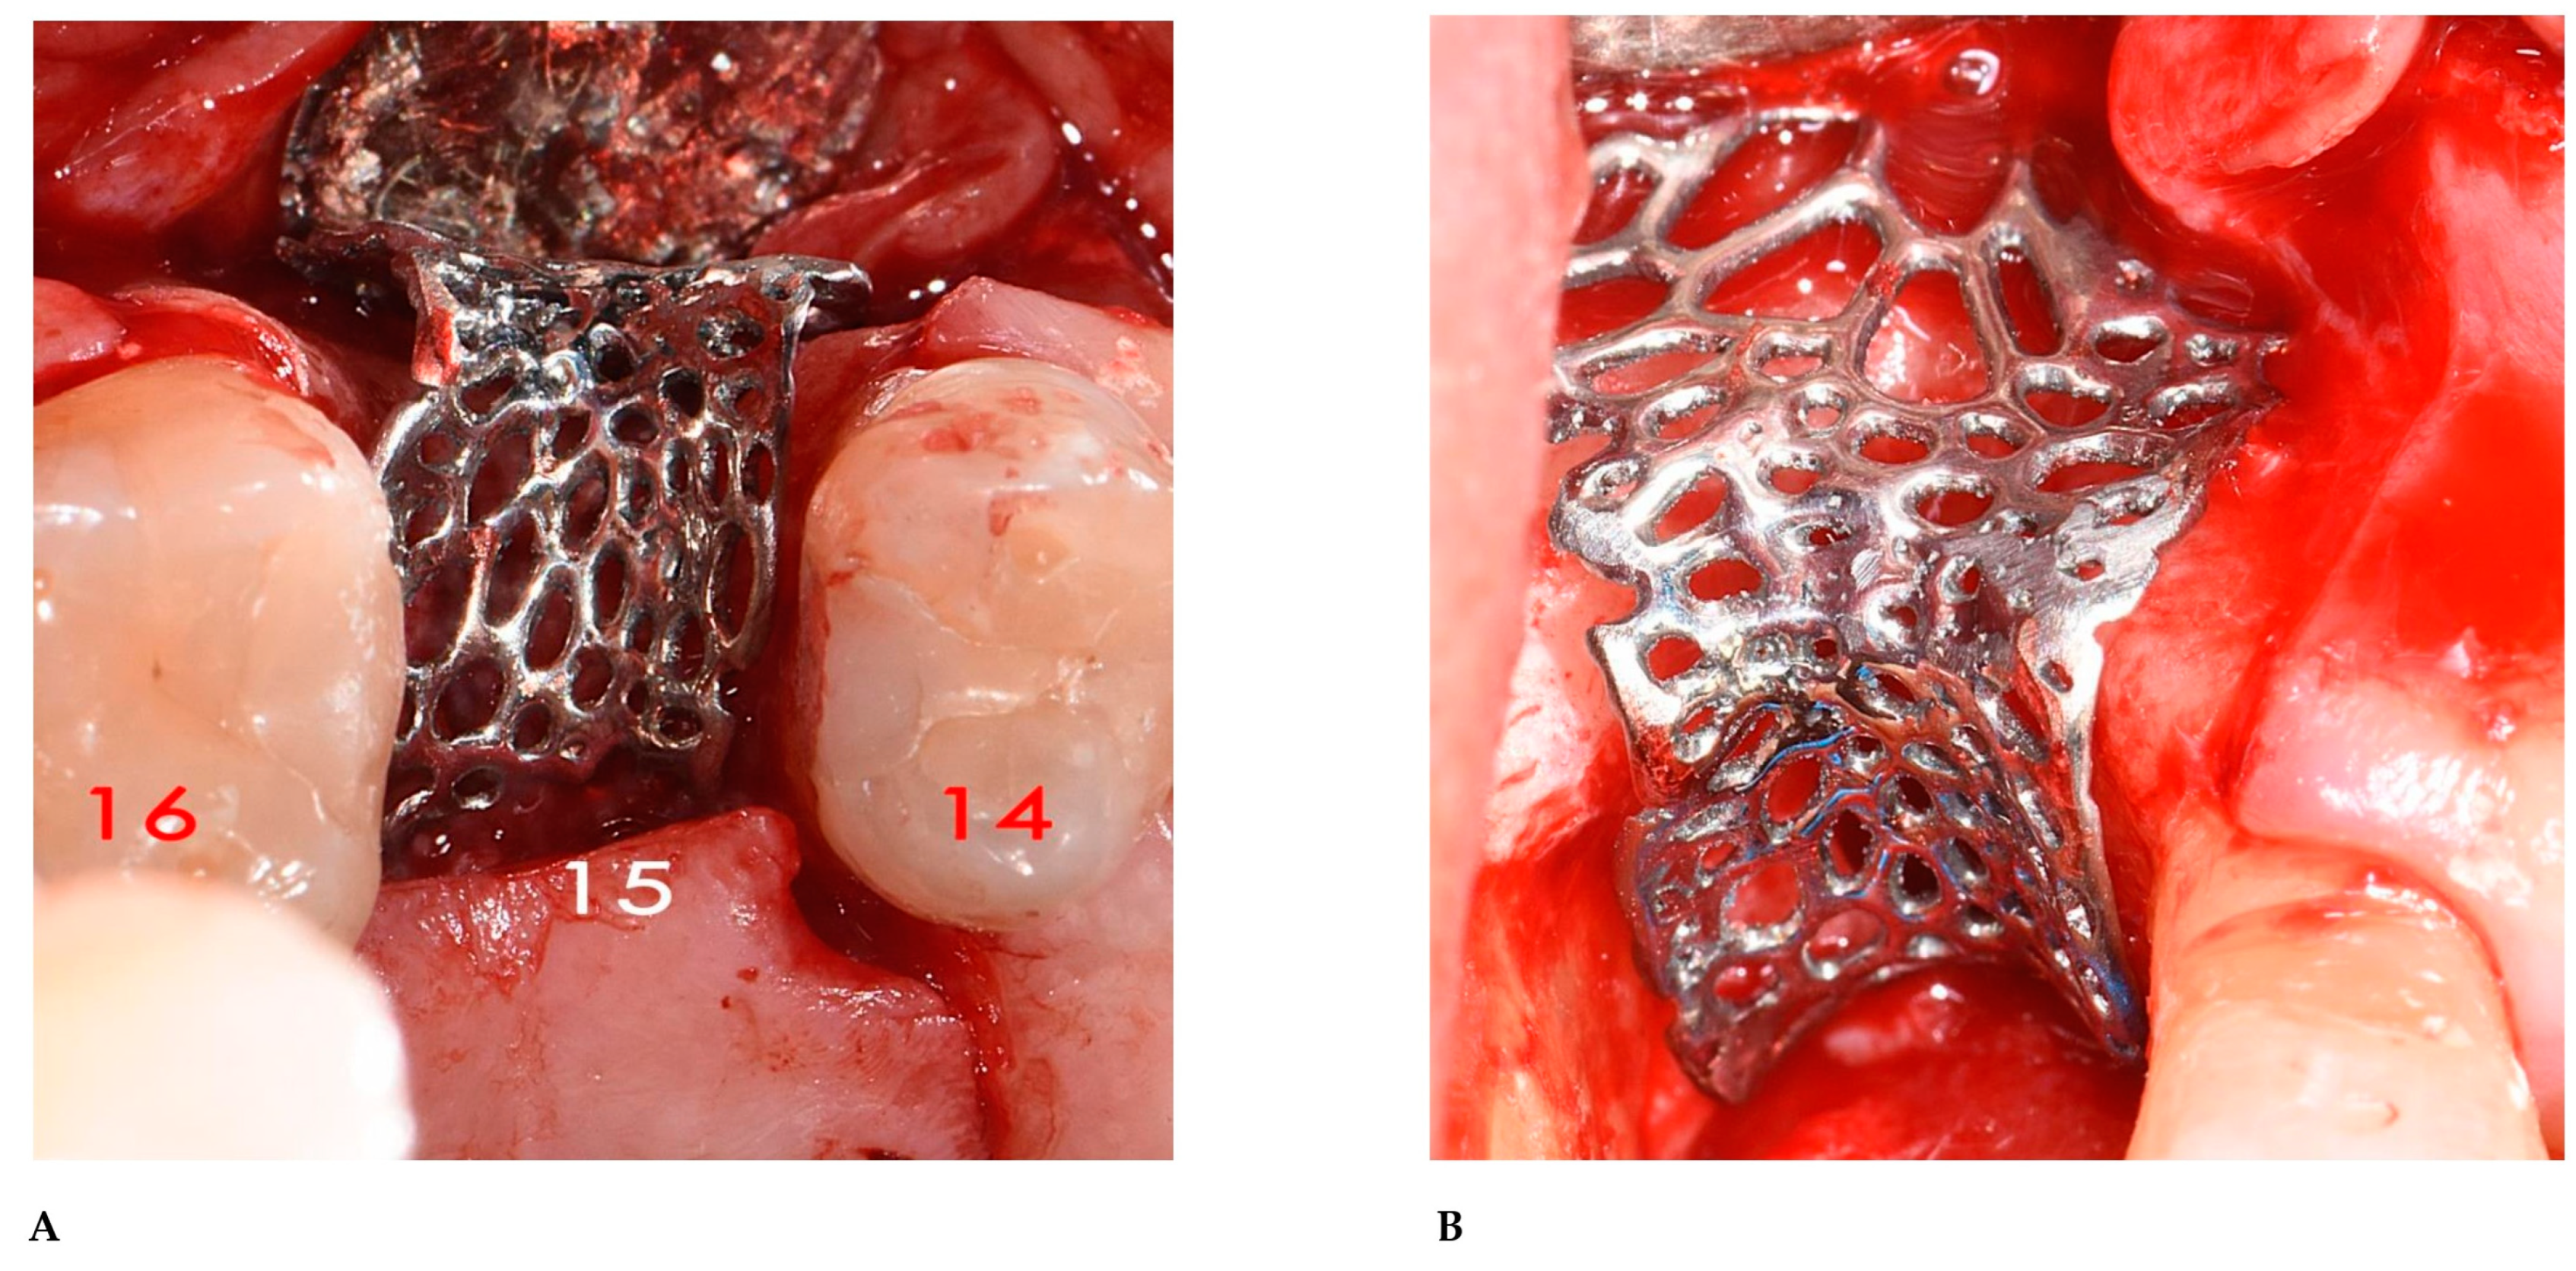

2.3. Surgical and Prosthetic Procedures

3. Results